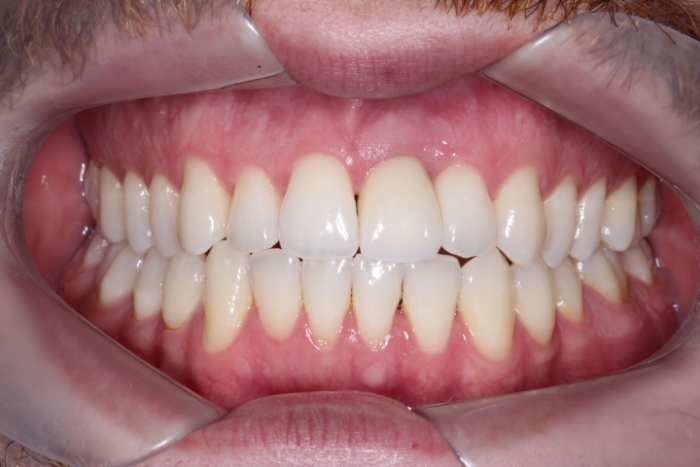

Foto Frontal com Protese definitiva 5 meses 21-11-15